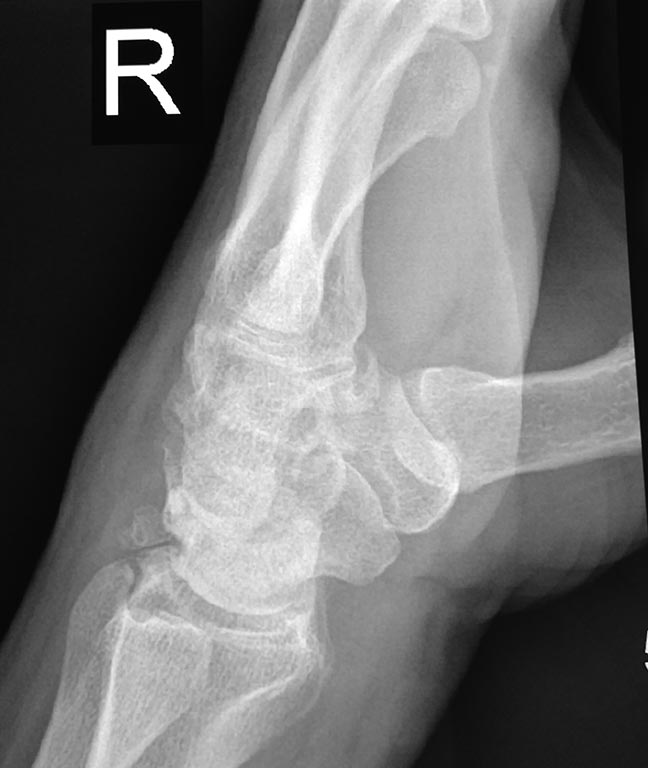

[Ortho] боли в лучезапястном суставе

проекции

Имя     : IMG_20170312_171912.jpg

Тип     : image/jpeg

Url     : http://weborto.net:8080/pipermail/ortho/attachments/20170313/b38b27b5/attachment-0003.jpg